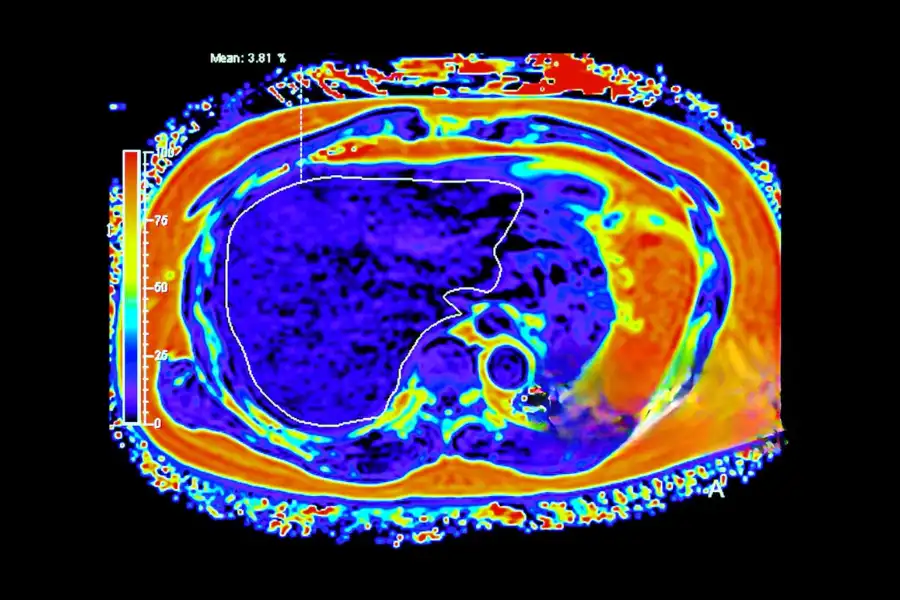

Контрастное усиление выполняется с помощью специального препарата на основе гадолиния, который вводится внутривенно и значительно повышает точность диагностики. Контраст помогает врачу различить здоровые и патологически изменённые ткани, так как накапливается в зонах с повышенным кровоснабжением — типичных для опухолей и метастазов печени.

Первичный рак печени, развивающийся из гепатоцитов. На МРТ с контрастом проявляется как очаг с интенсивным усилением в артериальной фазе и быстрым “вымытием” контраста в венозной. Характерны неровные контуры и признаки сосудистой инвазии.

Метастазы в печени

На МРТ с контрастом видны как множественные округлые очаги с контрастным ободком по периферии и гипоинтенсивным центром (зона некроза). Это наиболее частый тип поражений печени при онкологических заболеваниях других органов.

По характеру накопления контраста врач определяет природу опухоли, стадию заболевания и выбирает оптимальную тактику лечения без необходимости в биопсии.